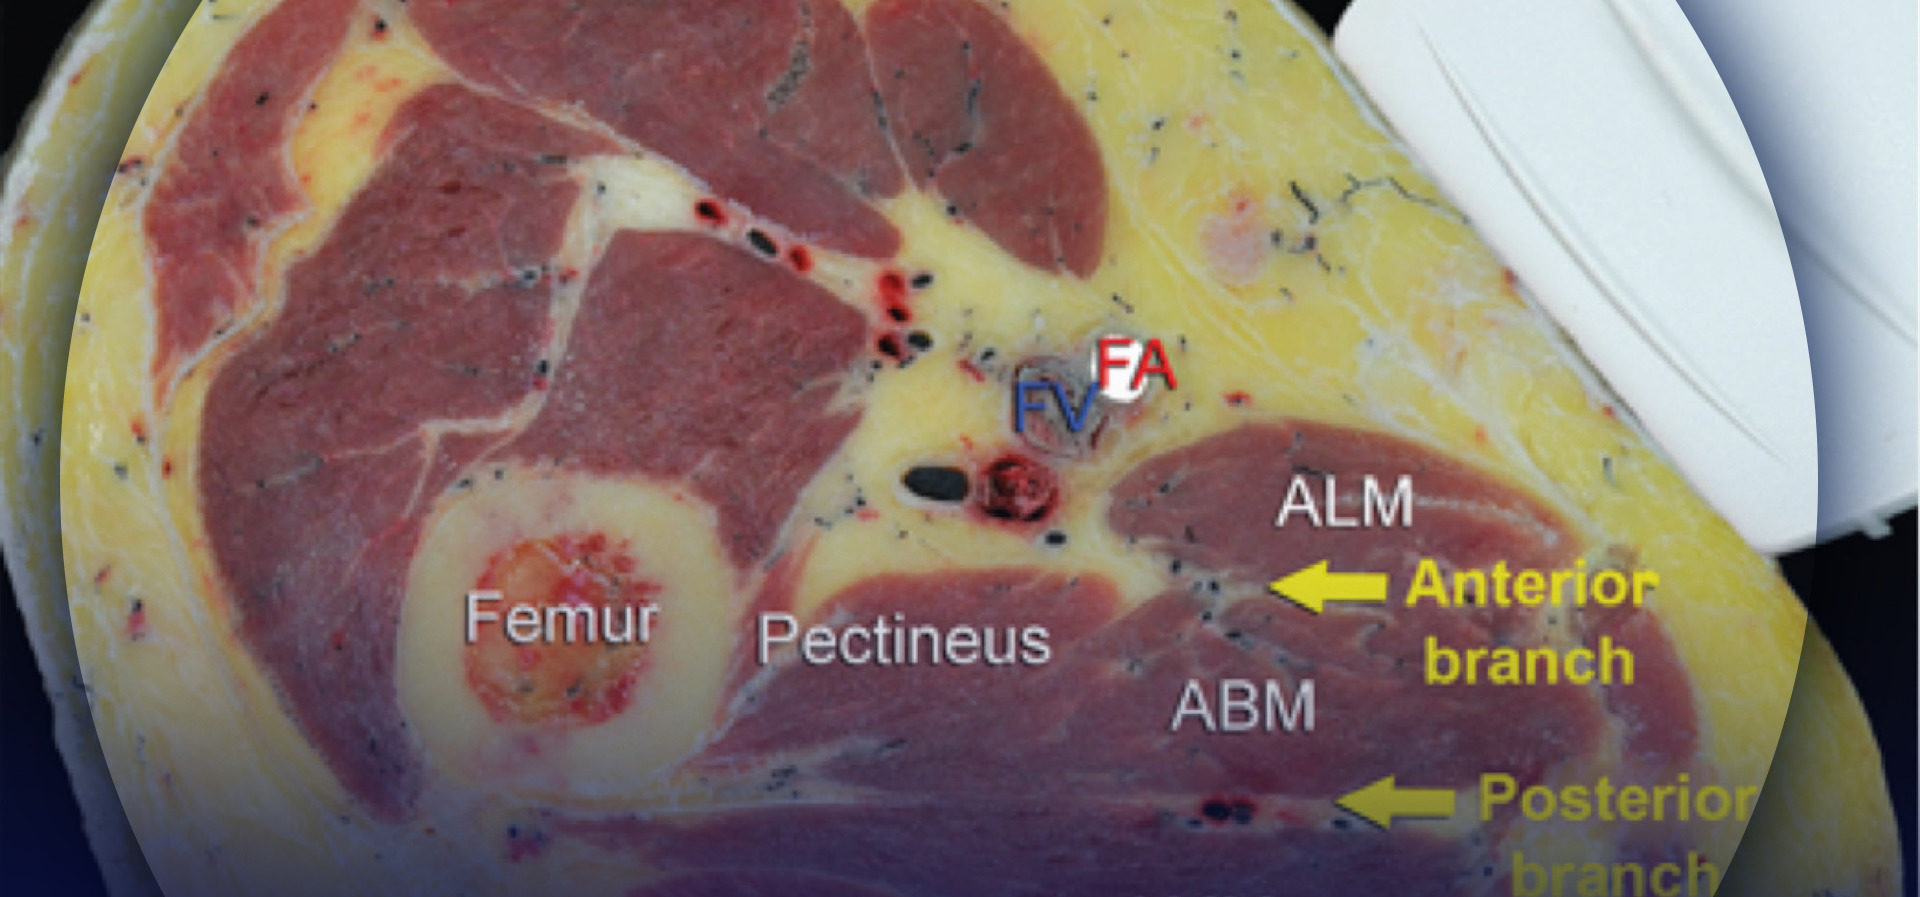

The anatomy of the sciatic nerve in the popliteal fossa is variable, and the division into the tibial nerve (TN) and common peroneal nerve (CPN) occurs at an inconstant distance from the popliteal crease (Figure 1). With nerve stimulator–based techniques, larger volumes (eg, > 40 mL) of local anesthetic have been used to increase the chance of nerve block success.

FIGURE 1. Cross-sectional anatomy of the sciatic nerve in the popliteal fossa. Shown are the common peroneal nerve (CPN), tibial nerve (TN), popliteal artery (PA), popliteal vein (PV), femur, biceps femoris muscle (BFM), semimembranosus muscle (SmM), and semitendinosus (StM) muscle.